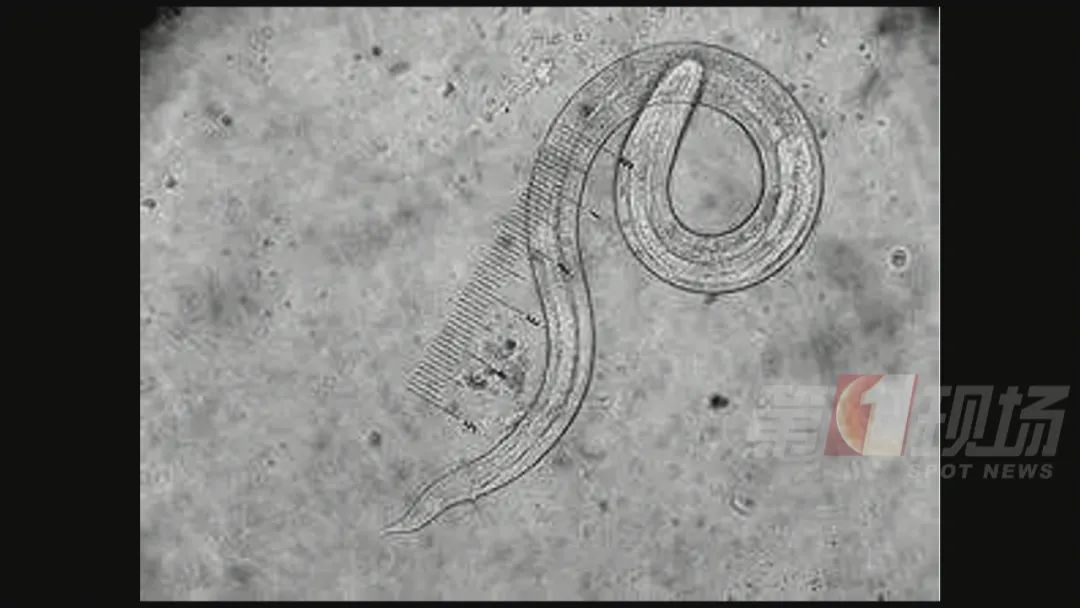

▲广州管源圆寄生虫这是一种十分罕见的寄生虫疾病

广州管圆线虫病广州管圆线虫是1933年由陈心陶首次在广州黑家鼠及褐家鼠体内发现 , 并命名为广州肺线虫 , 1946年由Dougherty最后命名为广州管圆线虫 。

这种寄生虫主要侵犯人体中枢神经系统 , 表现为嗜酸粒细胞增多性脑膜炎或脑膜脑炎、脊髓炎等 , 也可损害肺、眼和鼻 , 严重者可使人致死或致残 。